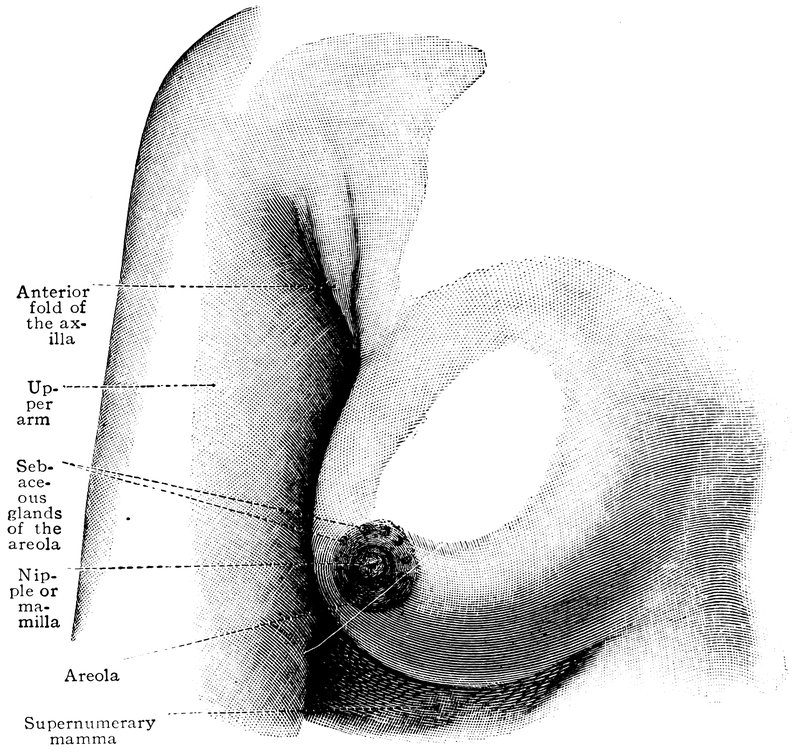

| 46. | The breast of a virgin aged eighteen years | 73 |

| 47. | Horizontal section through the female breast | 75 |

The beauty of woman, a prominent secondary sexual character, makes its first appearance at puberty, when the girl’s form, hitherto undifferentiated in its external bodily configuration, begins to assume a soft and rounded appearance, when the features become regular, the breasts enlarge, and the pubic hair begins to grow—when, in short, to the primary sexual characters already existing, the secondary sexual characters are superadded.

Feminine beauty continues to increase until the attainment of sexual maturity. In her third decade woman arrives at the acme of her sexual life and at the same time attains the perfection of her beauty.

The ensuing sexual phases, pregnancy, parturition, and lactation, entail a decline in beauty, not rapid indeed, but advancing gradually, with the slow yet sure-footed pace of time. The organic revolutions accompanying these processes leave traces recorded upon the surface of the body in conspicuous and indelible characters. The illnesses, also, which so often accompany the fulfilment of sexual functions, in injuring health impair also beauty.

A woman who has given birth to and nursed an infant begins to lay on fat, and this tendency to obesity becomes more pronounced as the climacteric period approaches. The breasts become inelastic and pendent, the abdomen becomes ungracefully prominent; the tonicity of the entire organism gradually declines, and, in consequence of the loss of elasticity in the subcutaneous cellular tissue, the dreaded wrinkles make their appearance and the features become wizened. Beauty is a thing of the past. With the cessation of the sexual life the external secondary sexual characters disappear, and the old woman is even farther removed than the old man from our conception of beauty.